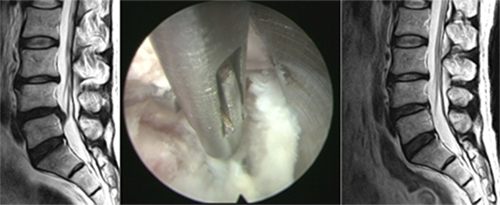

요통, 경추통, 방사통, 척추 골절, 척추 디스크, 척추관협착증, 척추전방전위증,신경차단술, 척추신경성형술, 내시경하 수핵제거술, 척추고정유합술 등

요통, 경추통, 방사통, 척추 골절, 척추 디스크, 척추관협착증, 척추전방전위증, 신경차단술, 척추신경성형술, 디스크고주파 감압술, 양방향 / 단일공 내시경하 수핵제거술, 척추 풍선복원술, 경추/요추 퇴행성질환 교정술 등